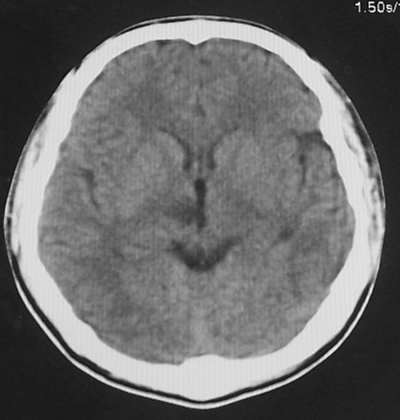

患者、男、18y,头痛5天入院。

左小脑、右丘脑区低密度影,无明显强化及占位表现,男18y,先考虑脑部炎性病变,如脑炎、血行播散性感染等,建议结合临床如脑脊液检验。

单独看左侧小脑半球的不规则形囊性低密度灶,从发病部位、年龄以及无强化、无占位效应的特点可以考虑毛细胞瘤型星形细胞瘤。同样,如果单独看右侧丘脑的近圆形低密度,也可以考虑囊变形星形细胞瘤。只是胶质细胞瘤一般为单发直接浸润、蔓延生长,而不是在脑内同时出现多个病灶,且瘤周没有一点儿水肿,暂时不予以考虑。

脑炎倒是首先可以考虑,只是临床症状、病史不很符合,建议狼兄仔细了解病史以及其他临床资料。

同时,现在已经进入冬天,一氧化碳中毒也需要考虑进去。不知道增强是什么时间做的,与平扫间隔几天?如果中间时间比较久而且进行吸氧等治疗,则平扫所示右侧颞叶密度比较低、右侧小脑半球以及脑桥也似有片囊状低密度,但在增强却没有发现就可以比较合理的解释了。